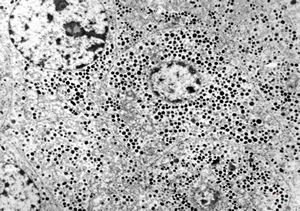

M, 38y. | pheochromocytoma